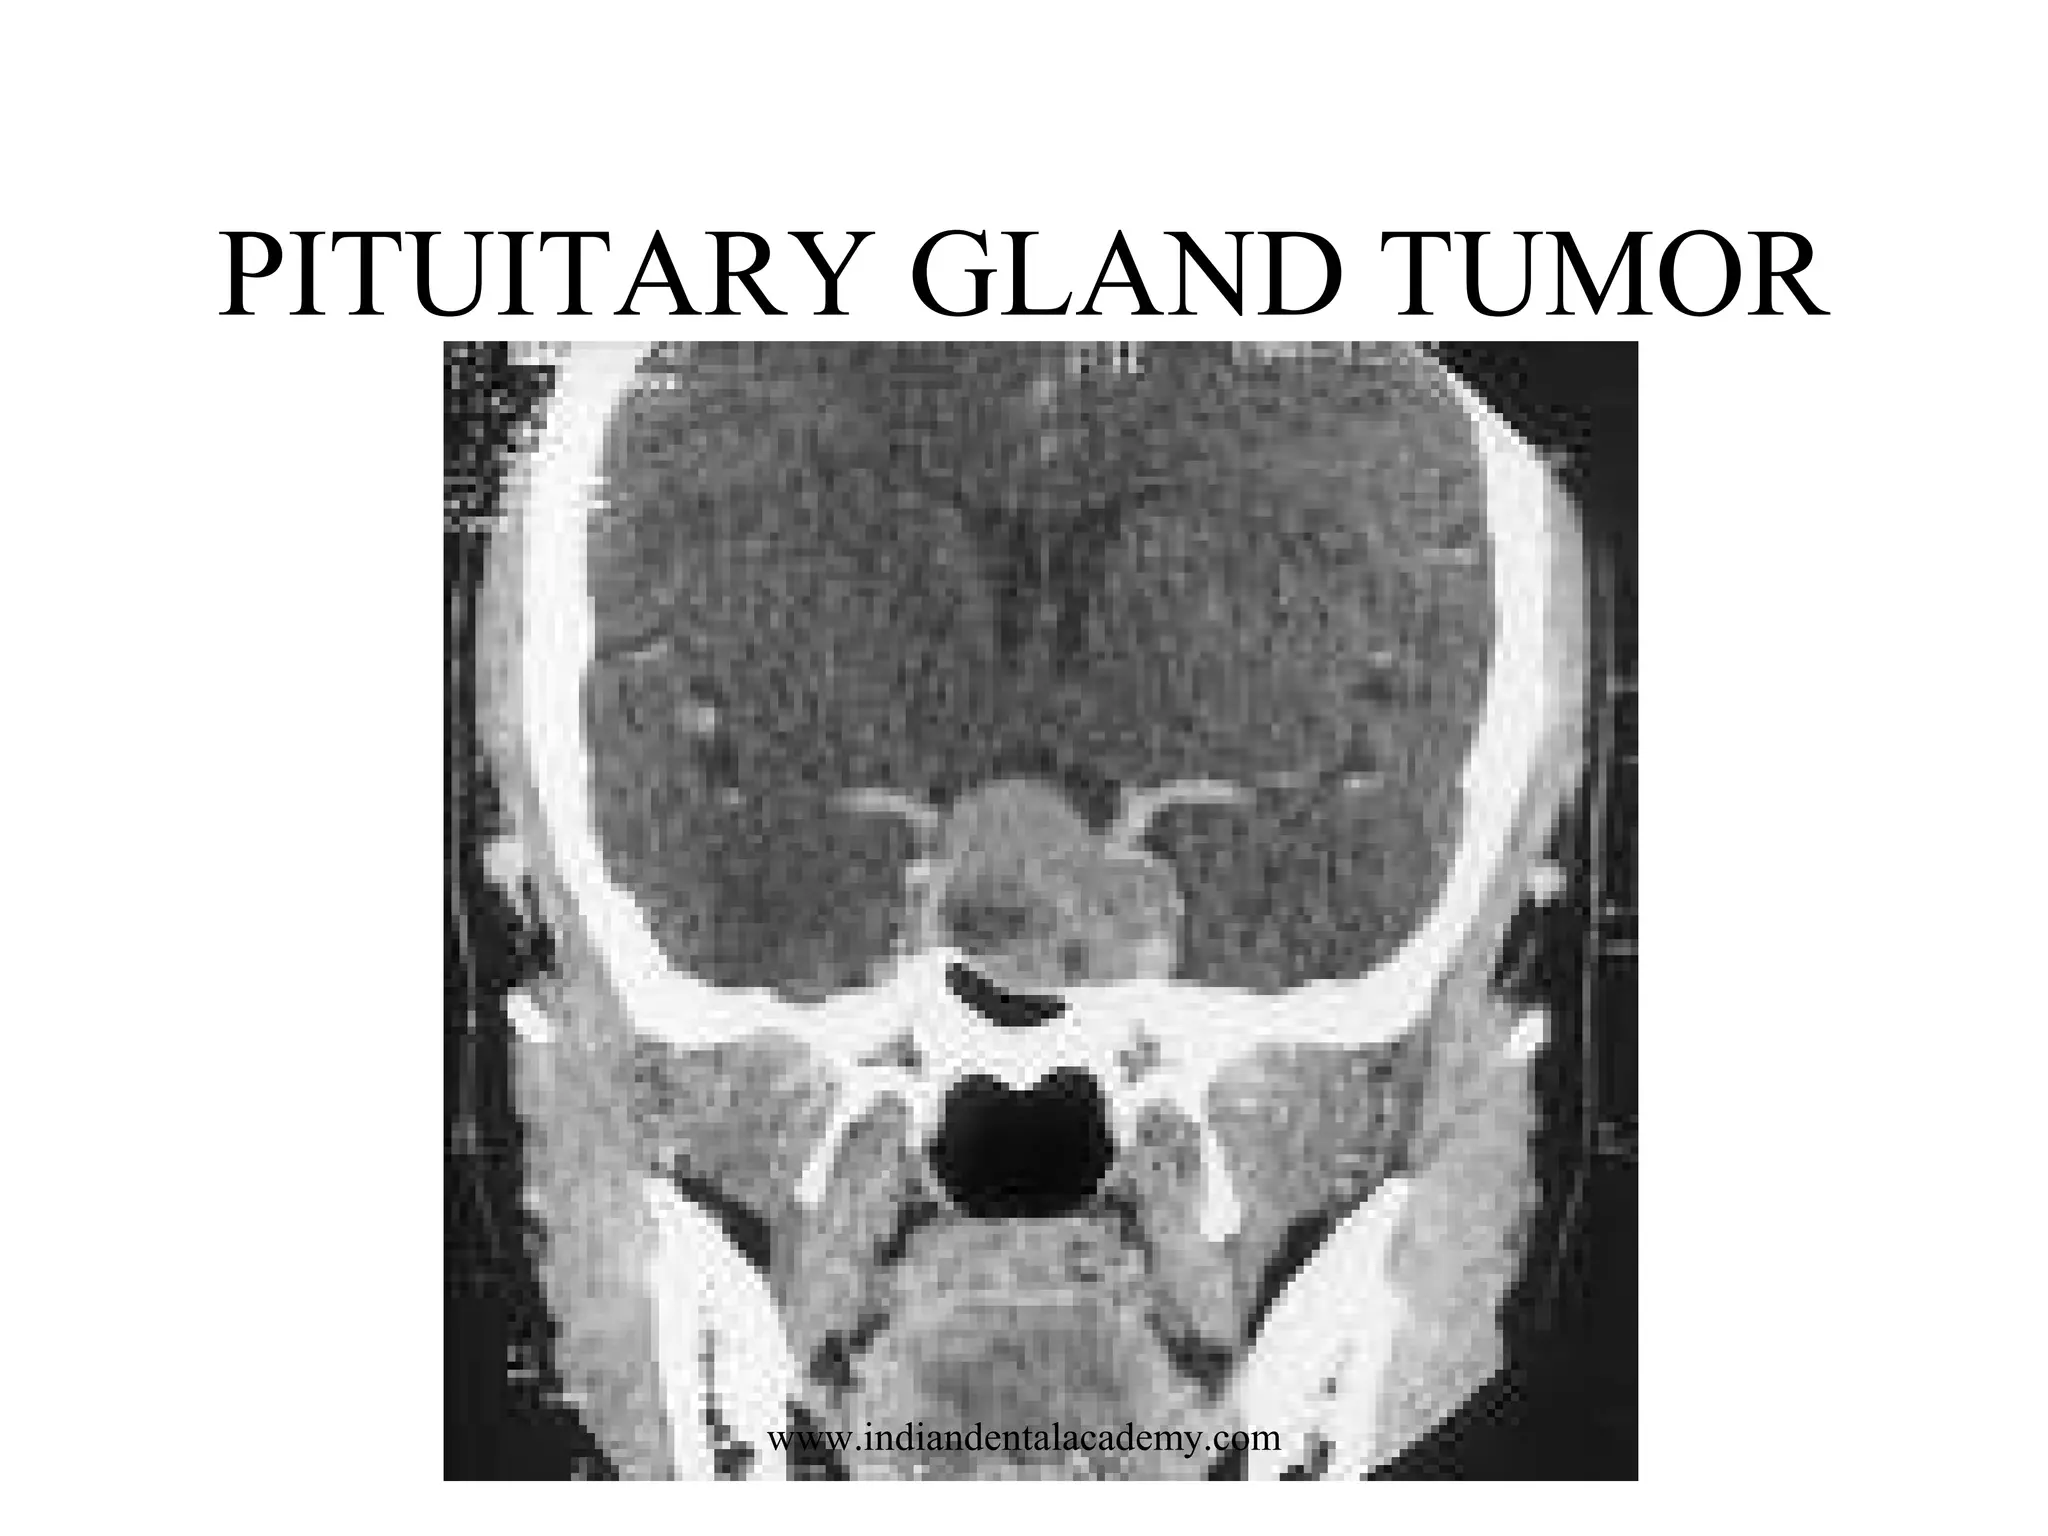

PITUITARY GLAND TUMOR

www.indiandentalacademy.com

PITUITARY AND SELLA TURCICA

SCOUT: LATERAL

LANDMARK: OML

SLICE PLANE: CORONAL & AXIAL

I.V. CONTRAST: 100-140 ML

BREATH HOLD: NONE

SLICE THICKNESS: 1-1.5 mm

FILMING: BONE & SOFT TISSUE

DFOV

12